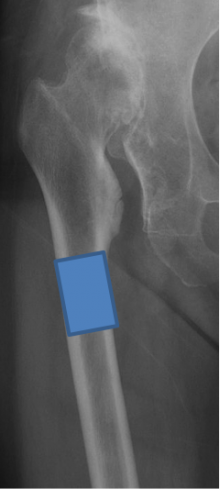

高位脱臼に対する人工関節

生まれつき股関節が脱臼した状態で気づかずに放置されていた場合、正常な股関節より高い位置に関節が形成されていることがあります(高位脱臼)。脱臼した側の足の長さは5~6cm短くなっていることが多く、関節が変形し、痛みが出やすい状態になります。

このような場合、大腿骨を数cm切り取り(短縮骨切り術)、正常な関節の位置に新しく人工関節を作り直しする手術を行います。